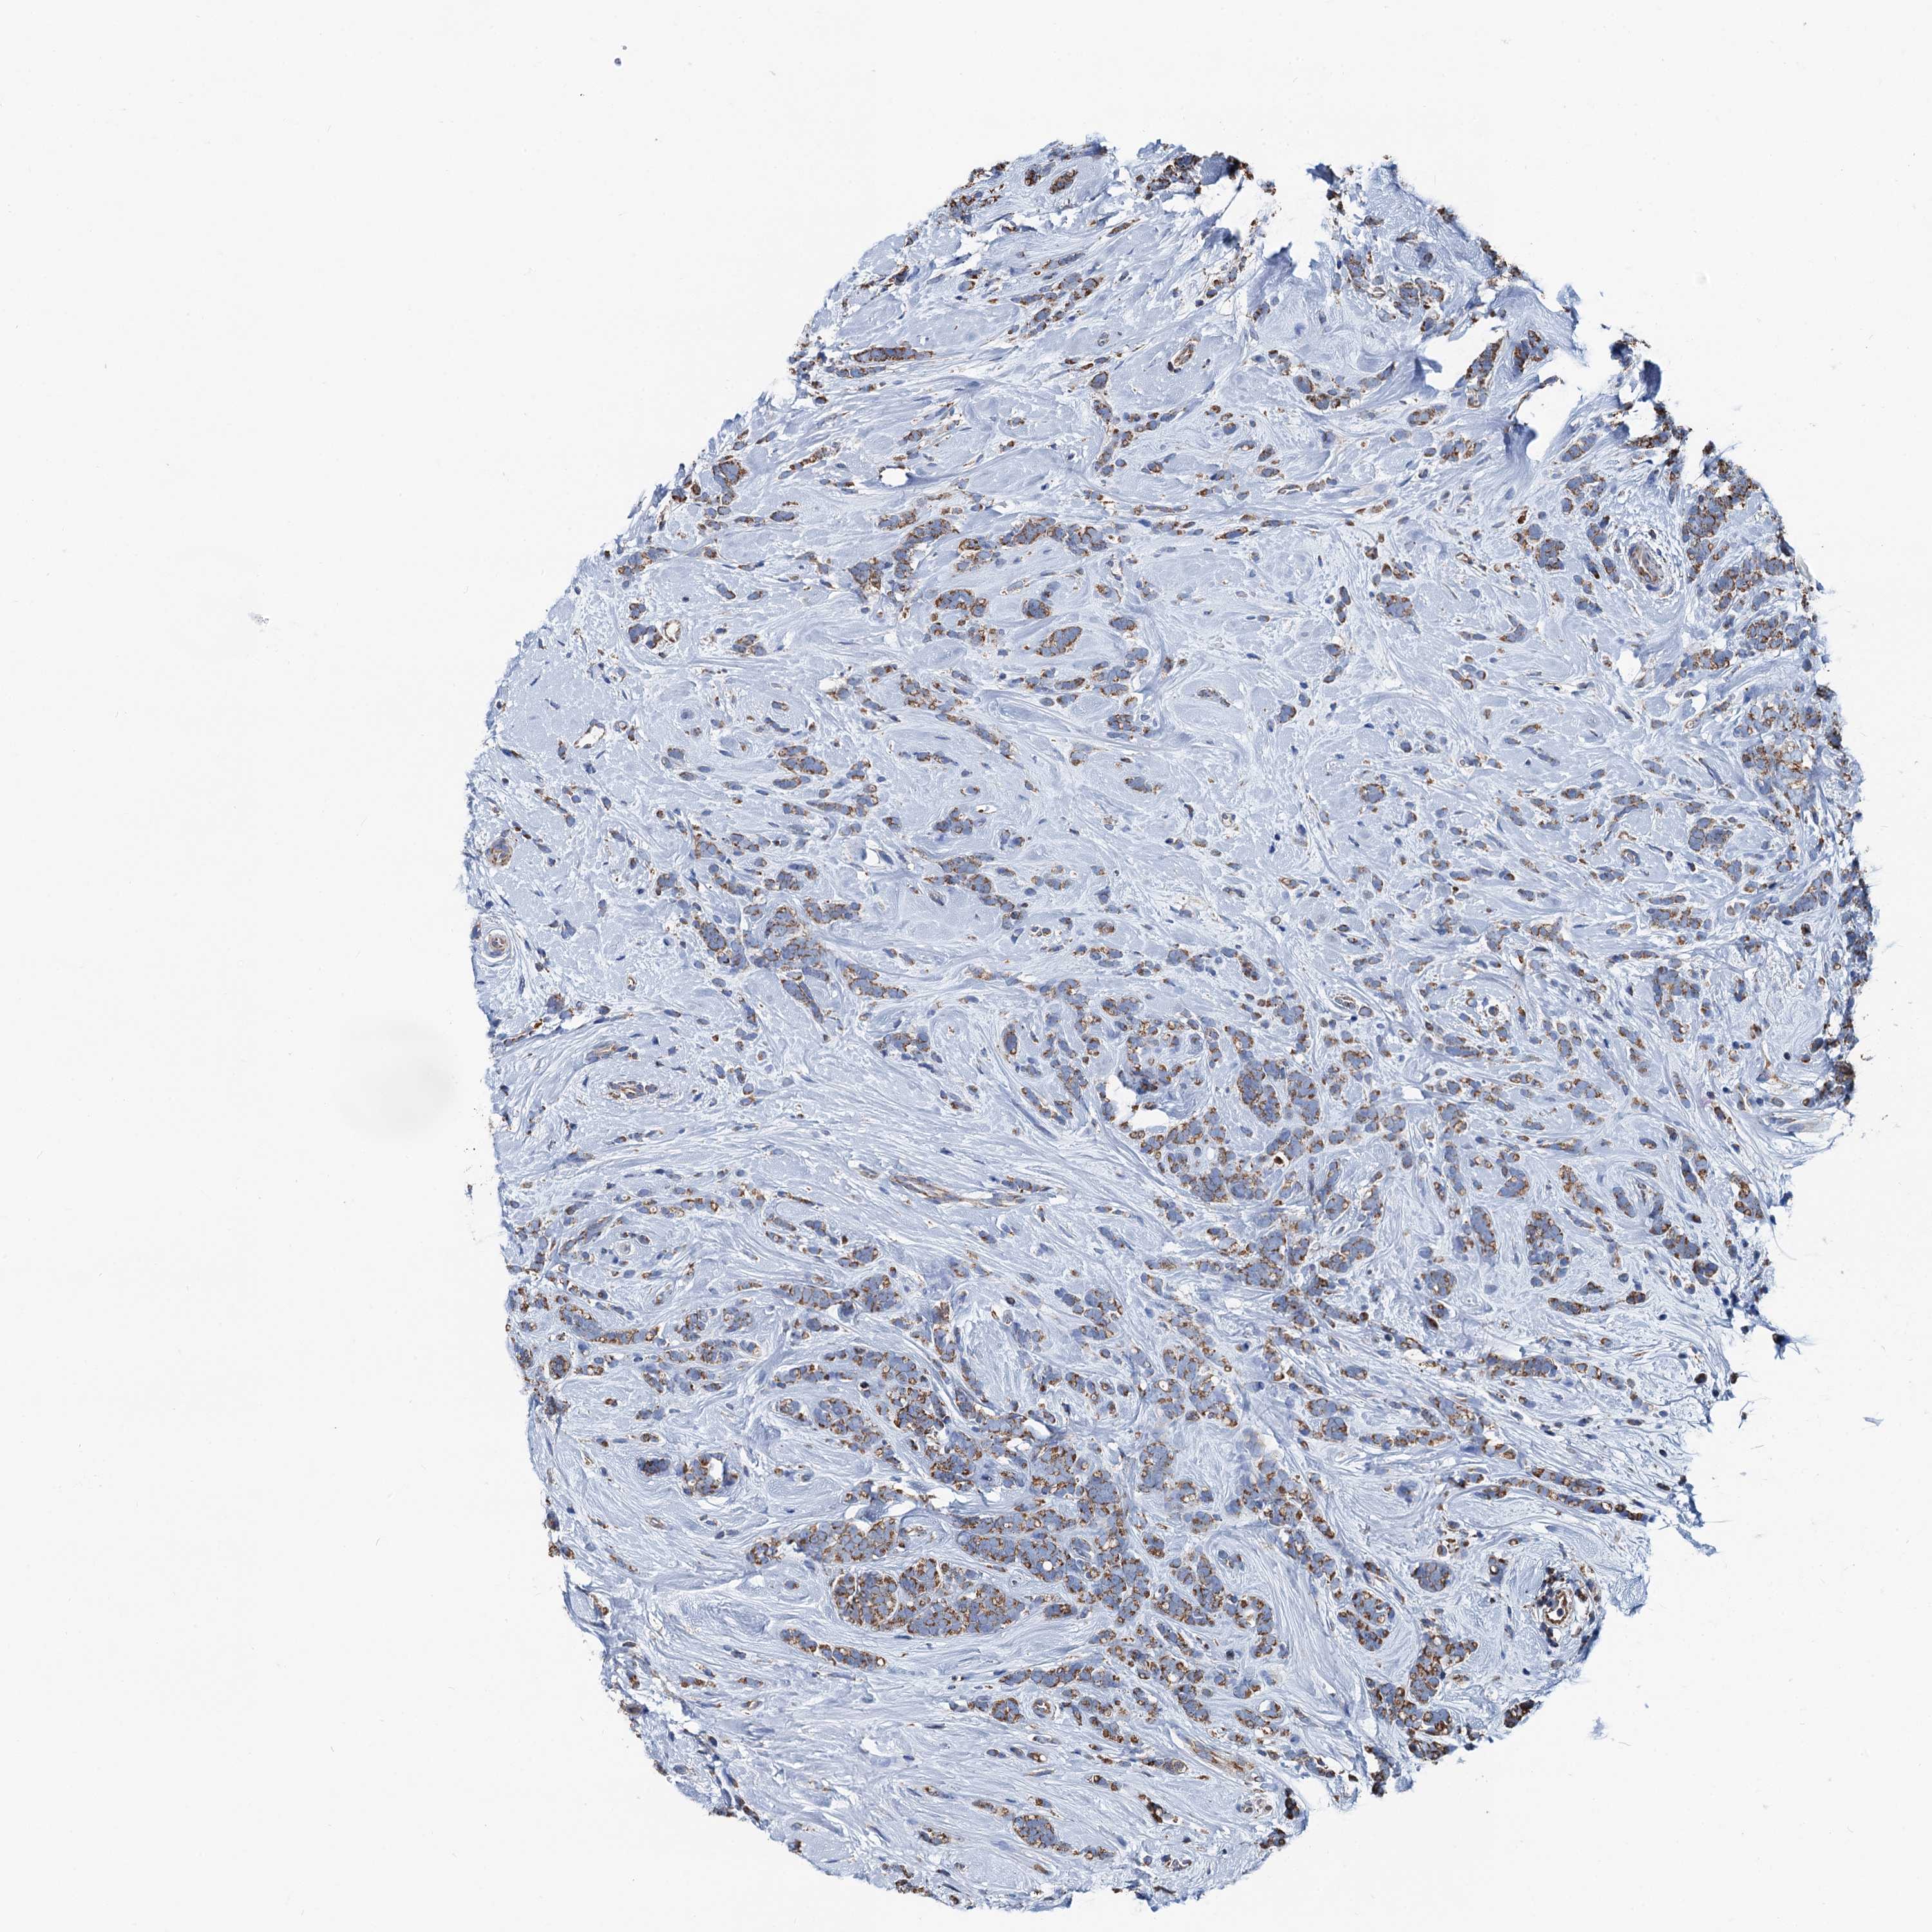

CANCER BREAST CANCER Show tissue menu

BRCA TCGA BRCA VALIDATION PROTEIN EXPRESSION